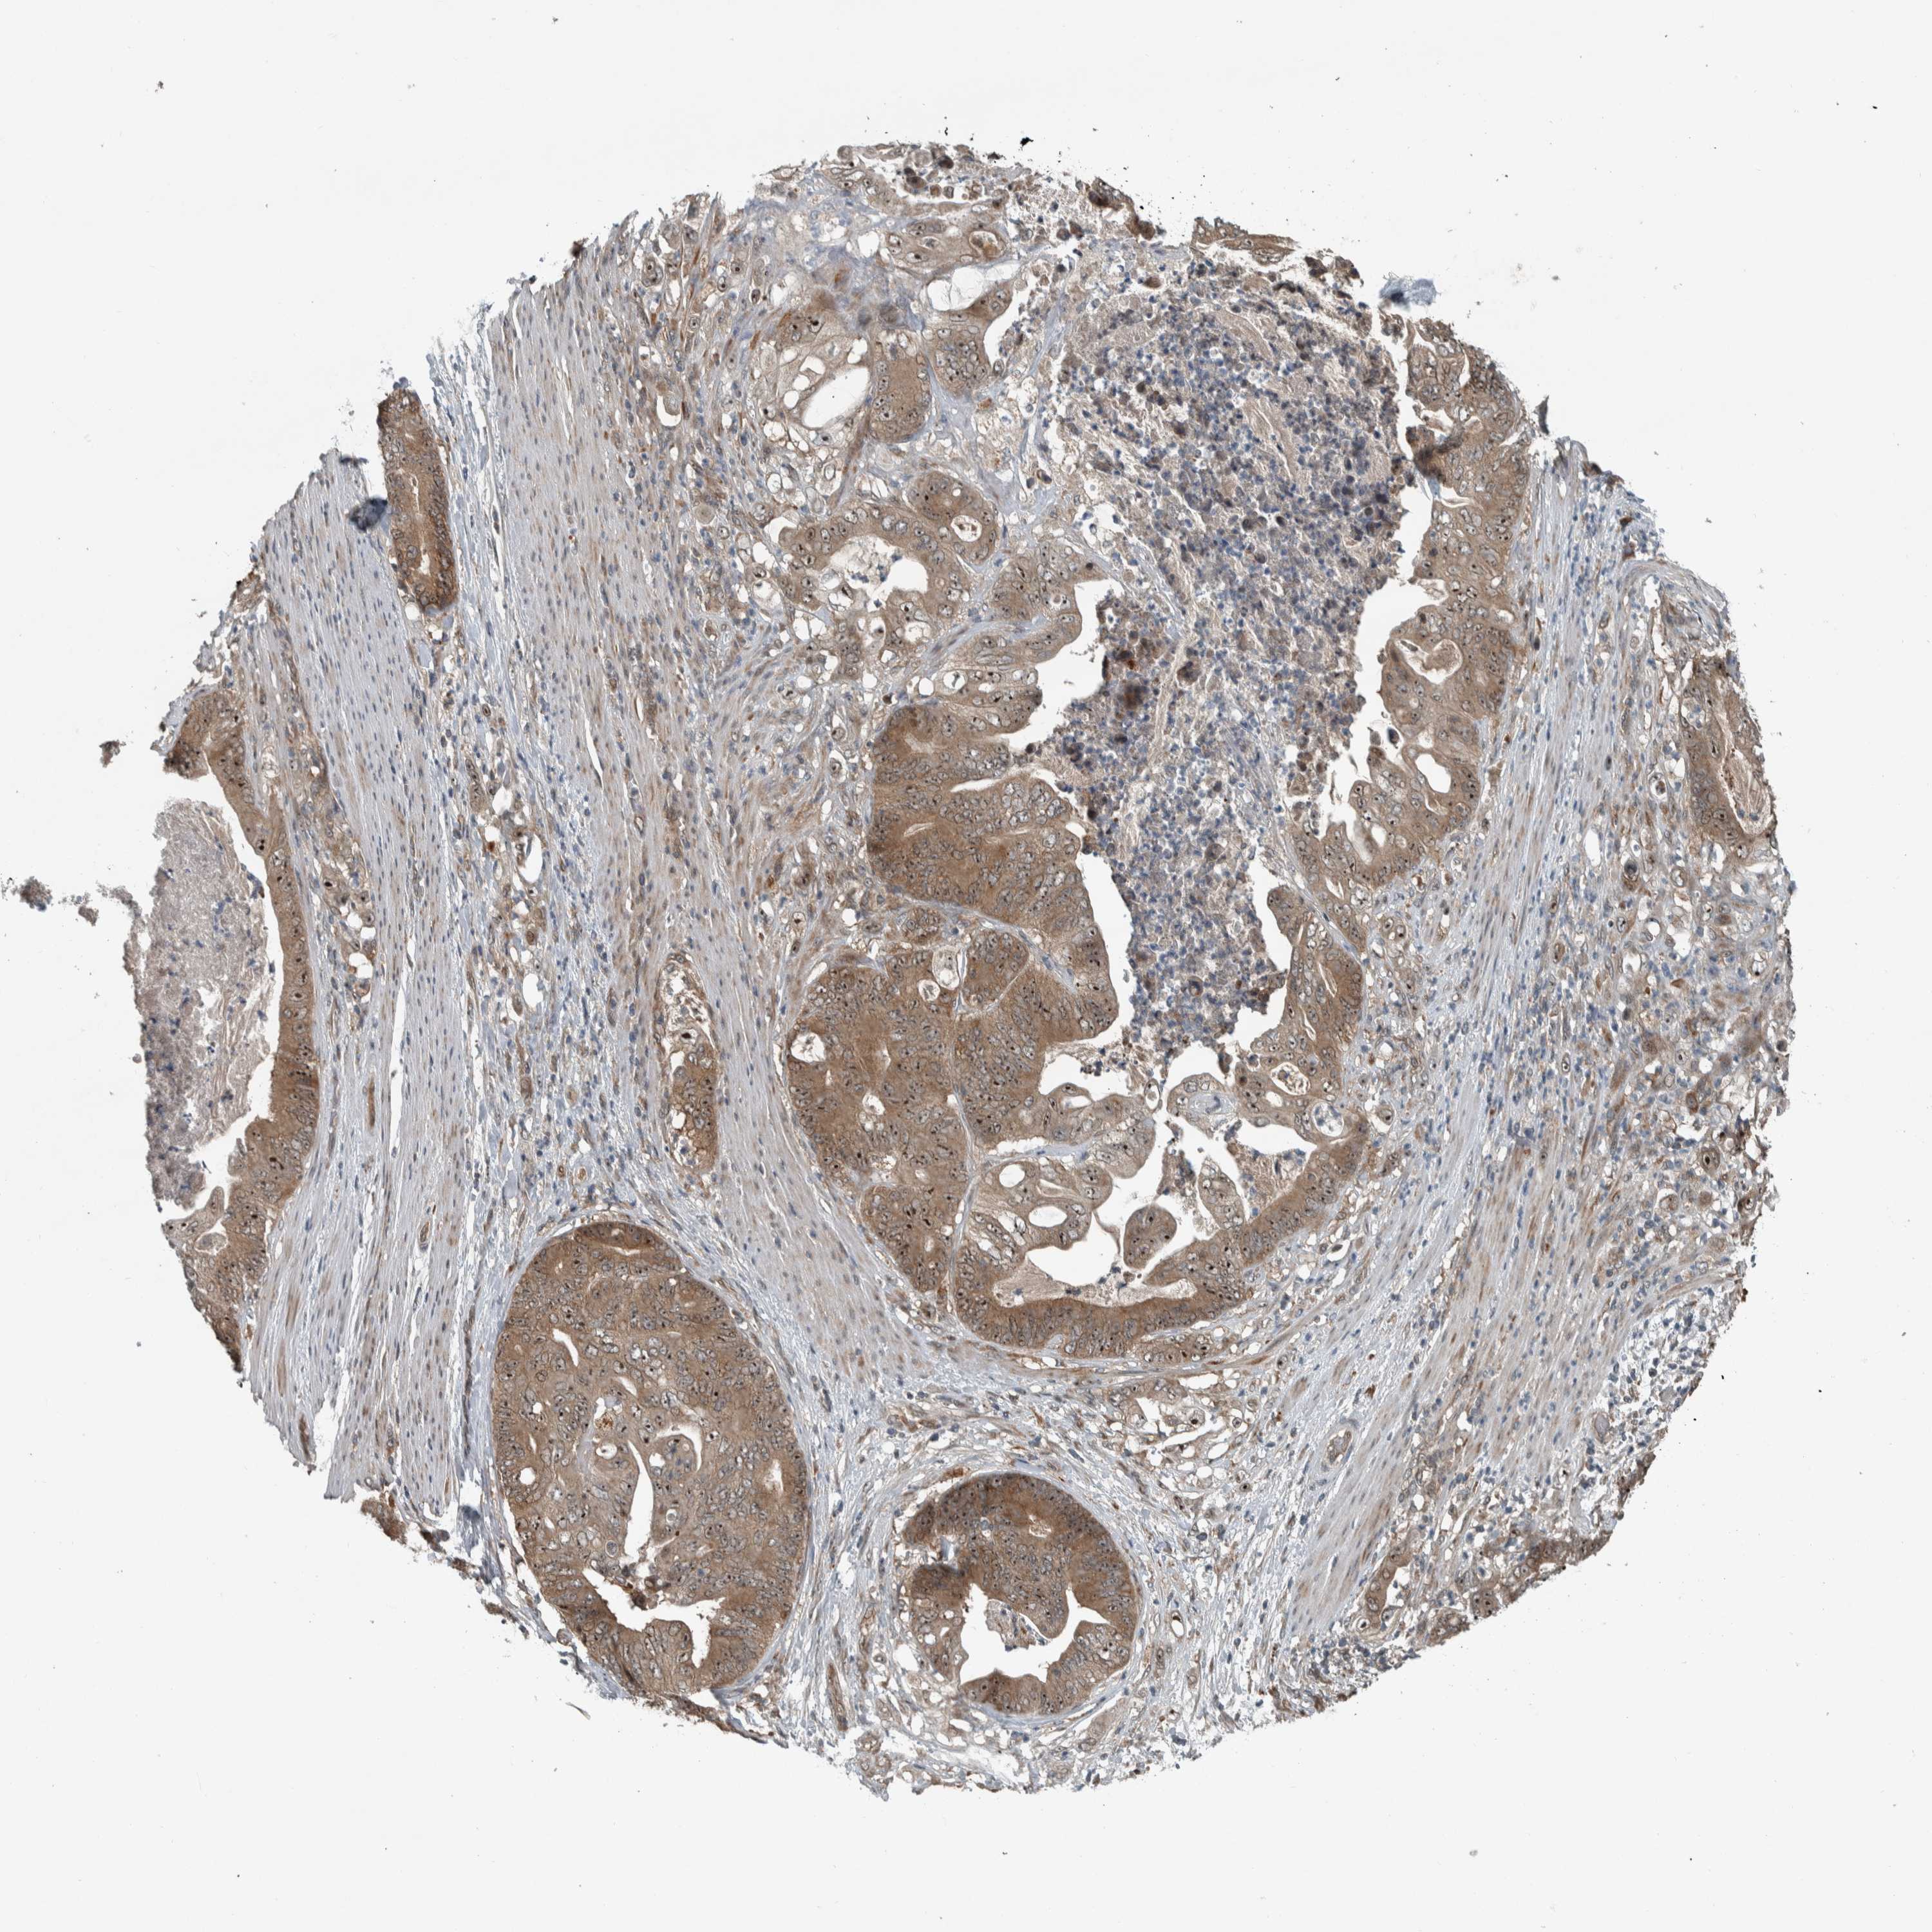

STOMACH CANCER - Protein expressioni

A mouse-over function shows sample information and annotation data. Click on an image to view it in a full screen mode. Samples can be filtered based on level of antibody staining by selecting one or several of the following categories: high, medium, low and not detected. The assay and annotation is described here.

Note that samples used for immunohistochemistry by the Human Protein Atlas do not correspond to samples in the TCGA dataset.

Antibody stainingi

Antibody staining in the annotated cell types in the current human tissue is reported as not detected, low, medium, or high, based on conventional immunohistochemistry profiling in selected tissues. This score is based on the combination of the staining intensity and fraction of stained cells.

Each image is clickable and will lead to virtual microscopy that enables deeper exploration of all samples and also displays staining intensity scores, fraction scores and subcellular localization as well as patient and tissue information for each sample.

Antibody HPA018402

Antibody HPA023959

Staining

High

Medium

Low

Not detected

Intensity

Strong

Moderate

Weak

Negative

Quantity

>75%

75%-25%

<25%

None

Location

Nuclear

Cytoplasmic/membranous

Cytoplasmic/membranous,nuclear

Adenocarcinoma, NOS